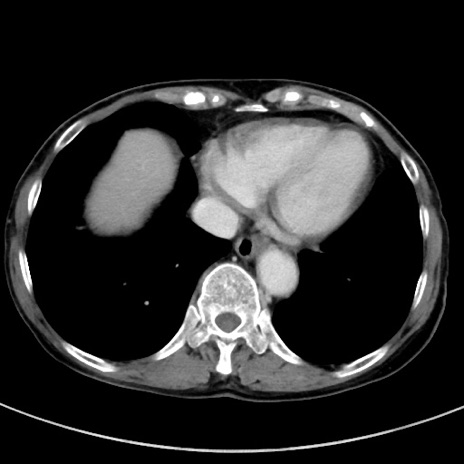

冠状断像